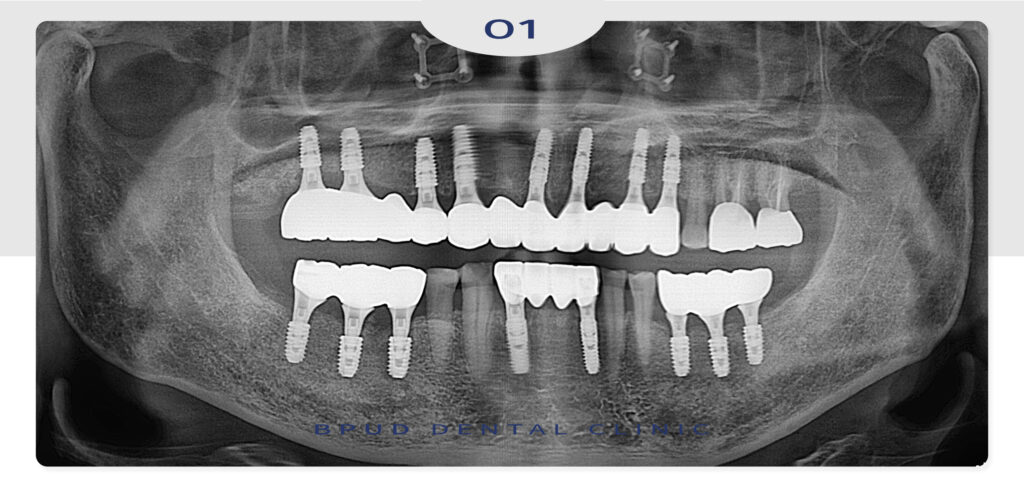

환자분께서 자주 내원이 어려우셨던 상황을

고려하여 하루에 위, 아래 16개 임플란트를

식립하였는데요.

다만 환자분과 같은 풀케이스는

단일 임플란트 식립에 비해

난이도가 높은 치료로 고혈압이나 당뇨 등

만성질환이 있는 분들의 경우

수술 전 전신 건강 상태에 대한

충분한 확인이 필요한데요.

특히 고령 환자분일수록 통증이나 출혈,

감염 등에 대한 관리가 중요하기 때문에

정밀 검진을 통해 개인의 구강 상태와

전신 건강을 종합적으로 살펴본 뒤

치료 방향을 정하고 시술 이후에도

정기적인 관리가 이어져야 합니다.